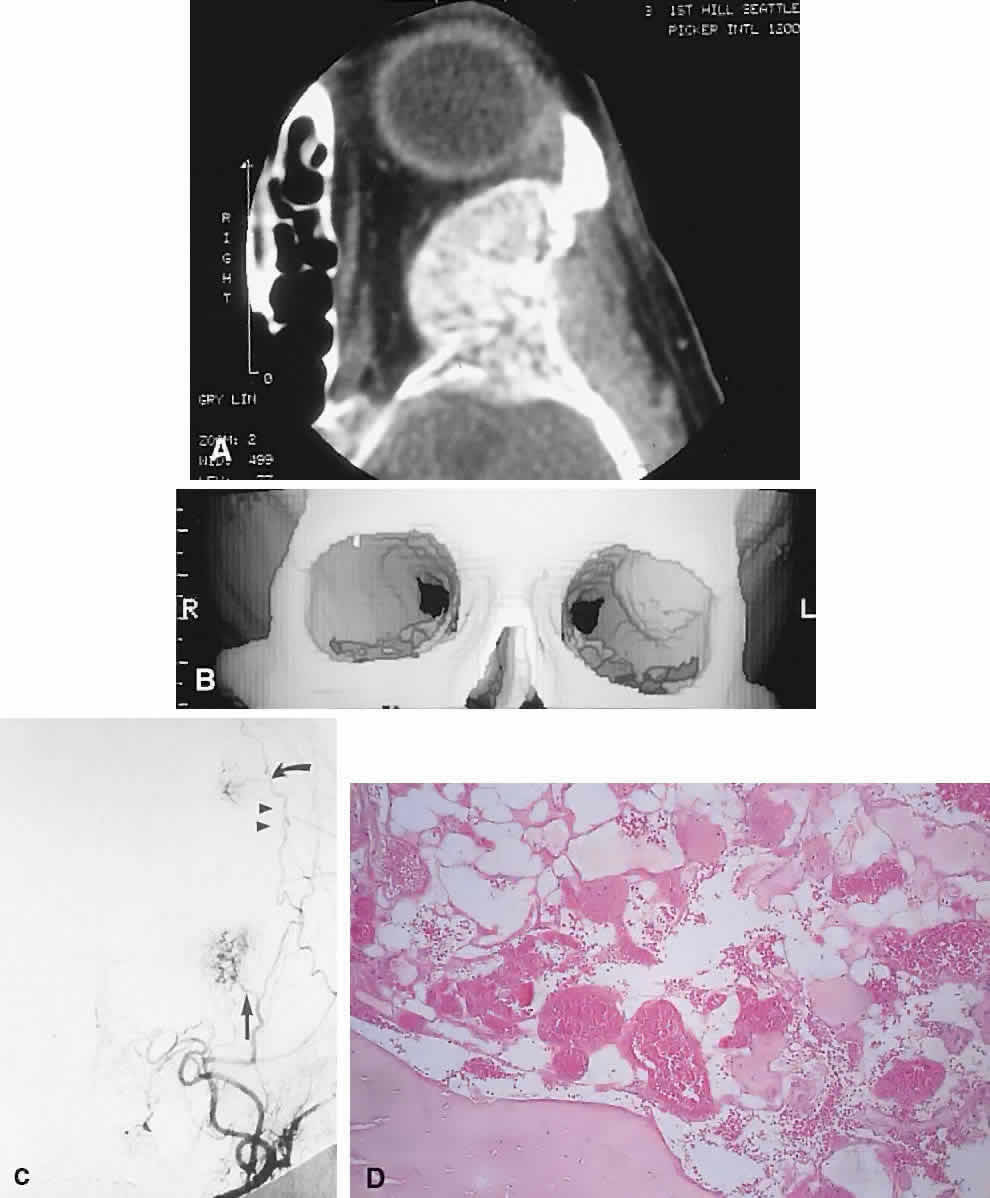

These benign vascular tumors of bone, like their counterparts in the orbital soft tissues, are probably hamartomatous in origin. They are common in the calvarium and spine but rare in the orbit. Any of the orbital bones may be involved, although the frontal bone is the most common site. Including one case of our own, there are 20 cases in the literature. The average age is in the fifth decade, with a slight female preponderance.151–155

IMAGING. Intraosseous hemangiomas present as well-defined, radiolucent masses that expand the inner and outer tables of the bone, often in an asymmetric fashion. Approximately half show the classic picture of a sunburst, striated, or honeycombed internal pattern (Fig. 13). On selective angiography, they appear as a tangle of vessels.155

Fig. 13. A 65-year-old woman with slowly progressive left proptosis. A. CT showed a well-defined, expansile lesion of the greater wing of the sphenoid, which demonstrated a spiculated internal pattern. B. A 3D CT illustrated the expansion of the bone of the lateral orbital wall. C. Subtraction angiography revealed a tangle of vessels at the site of the orbital mass (arrow) in addition to a smaller, more superior lesion in the frontal bone (curved arrow). After preoperative embolization, the mass was excised with a rim of normal bone. D. Histology showed an intraosseous hemangioma with large cavernous, endothelial-lined, blood-filled spaces (hematoxylin-eosin, × 20). (C from Rootman J, Kao SCS, Graeb DA: Multidisciplinary approaches to complicated vascular lesions of the orbit. Ophthalmology 9:1440–1446, 1992.)

HISTOPATHOLOGY. The specimen consists of soft, violaceous masses with intervening trabeculae of reactive bone. Microscopically, most are cavernous hemangiomas with large endothelial-lined, blood-filled vascular spaces.156

MANAGEMENT. Surgical treatment consists of excision with a rim of normal bone. Preoperative angiography should be performed and strong consideration given to embolization before resection, because these tumors can bleed in a profuse and persistent manner.155